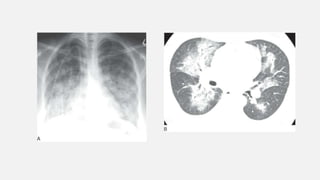

• #14 Ground-glass opacification on CT in an immunocompromised patient with Pneumocystis jiroveci infection.

• #24 Consolidation: patchy opacities. A: Chest radiograph in a patient with pulmonary edema due to renal failure shows patchy perihilar consolidation. B: Patchy areas of fluffy consolidation are seen on CT. The fluffy margins are due to variable involvement of alveoli at the edges of the pathologic process.

• #27 Perihilar “bat-wing” consolidation in pulmonary edema. A: Chest radiograph shows a distinct perihilar predominance of consolidation. The heart is enlarged. B: CT shows sparing of the lung periphery.